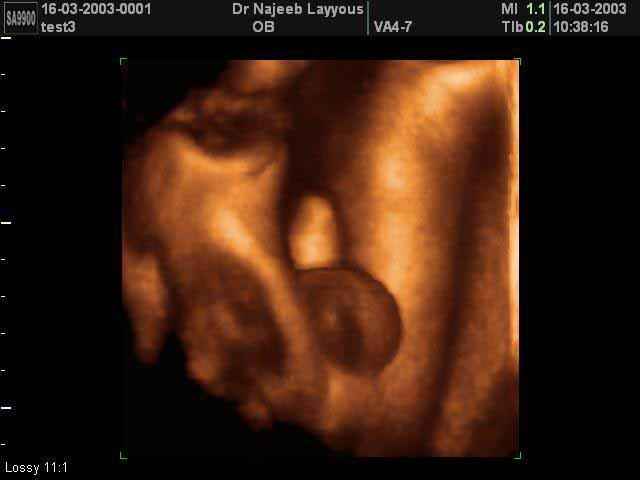

- 3D Photos échographie des parties du fœtus